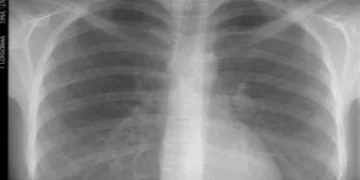

Рентген и флюорография — это два различных метода визуализации внутренних органов, которые используют рентгеновское излучение, но они имеют свои особенности и области применения. Рентгенография подразумевает получение статичного изображения, которое часто используется для диагностики различных заболеваний, таких как воспаления легких или переломы костей. В процессе рентгенографического исследования пациента помещают между рентгеновской пленкой и источником излучения, и изображение фиксируется на пленке или цифровом носителе.

Основное различие между этими методами заключается в их цели и детализации изображений. Рентгенография предоставляет более детализированные и четкие изображения, позволяя врачам проводить глубокий анализ состояния органов и тканей. Флюорография, несмотря на свою меньшую разрешающую способность, является удобным инструментом для быстрого выявления заболеваний и мониторинга состояния здоровья в массовом масштабе. Таким образом, выбор между этими методами зависит от конкретной ситуации и целей диагностики.